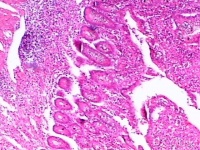

病理[编辑 | 编辑源代码]

总的来说,

克罗恩病为贯穿肠壁各层的增殖性病变,并侵犯肠系膜和局部淋巴结。病变局限于小肠(主要为末端回肠)和结肠者各占30%,二者同时累及各占40%,常为回肠和右半结肠病变。Crohn将病理变化分为急性炎症期、溃疡形成期、狭窄期和痰管形成期(穿孔期)。本病的病变呈节段分布,与正常肠段相互间隔,界限清晰,呈跳跃区(skiparea)的特征。急性期以肠壁水肿炎变为主;慢性期肠壁增厚、僵硬,受累肠管外形呈管状,其上端肠管扩张。粘膜面典型病变有:①溃疡:早期浅小溃疡,后成纵行或横行的溃疡,深入肠壁的纵行溃疡即形成较为典型的裂沟,沿肠系膜侧分布。肠壁可有脓肿。②卵石状结节:由于粘膜下层水肿和细胞浸润形成的小岛突起,加上溃疡愈合后纤维化和疤痕的收缩,使粘膜表面似卵石状。③肉芽肿:无干酩样变,有别于结核病。肠内肉芽肿系炎症刺激的反应,并非克罗恩病独有;且20%~30%病例并无肉芽肿形成,故不宜称为肉芽肿性肠炎。④瘘管和脓肿:肠壁的裂沟实质上是贯穿性溃疡,使肠管与肠管、肠管与脏器或组织(如膀耽、阴道、肠系膜或腹膜后组织等)之间发生粘连和脓肿,并形成内瘘管。如病变穿透肠壁,经腹壁或肛门周围组织而通向体外,即形成外瘘管。